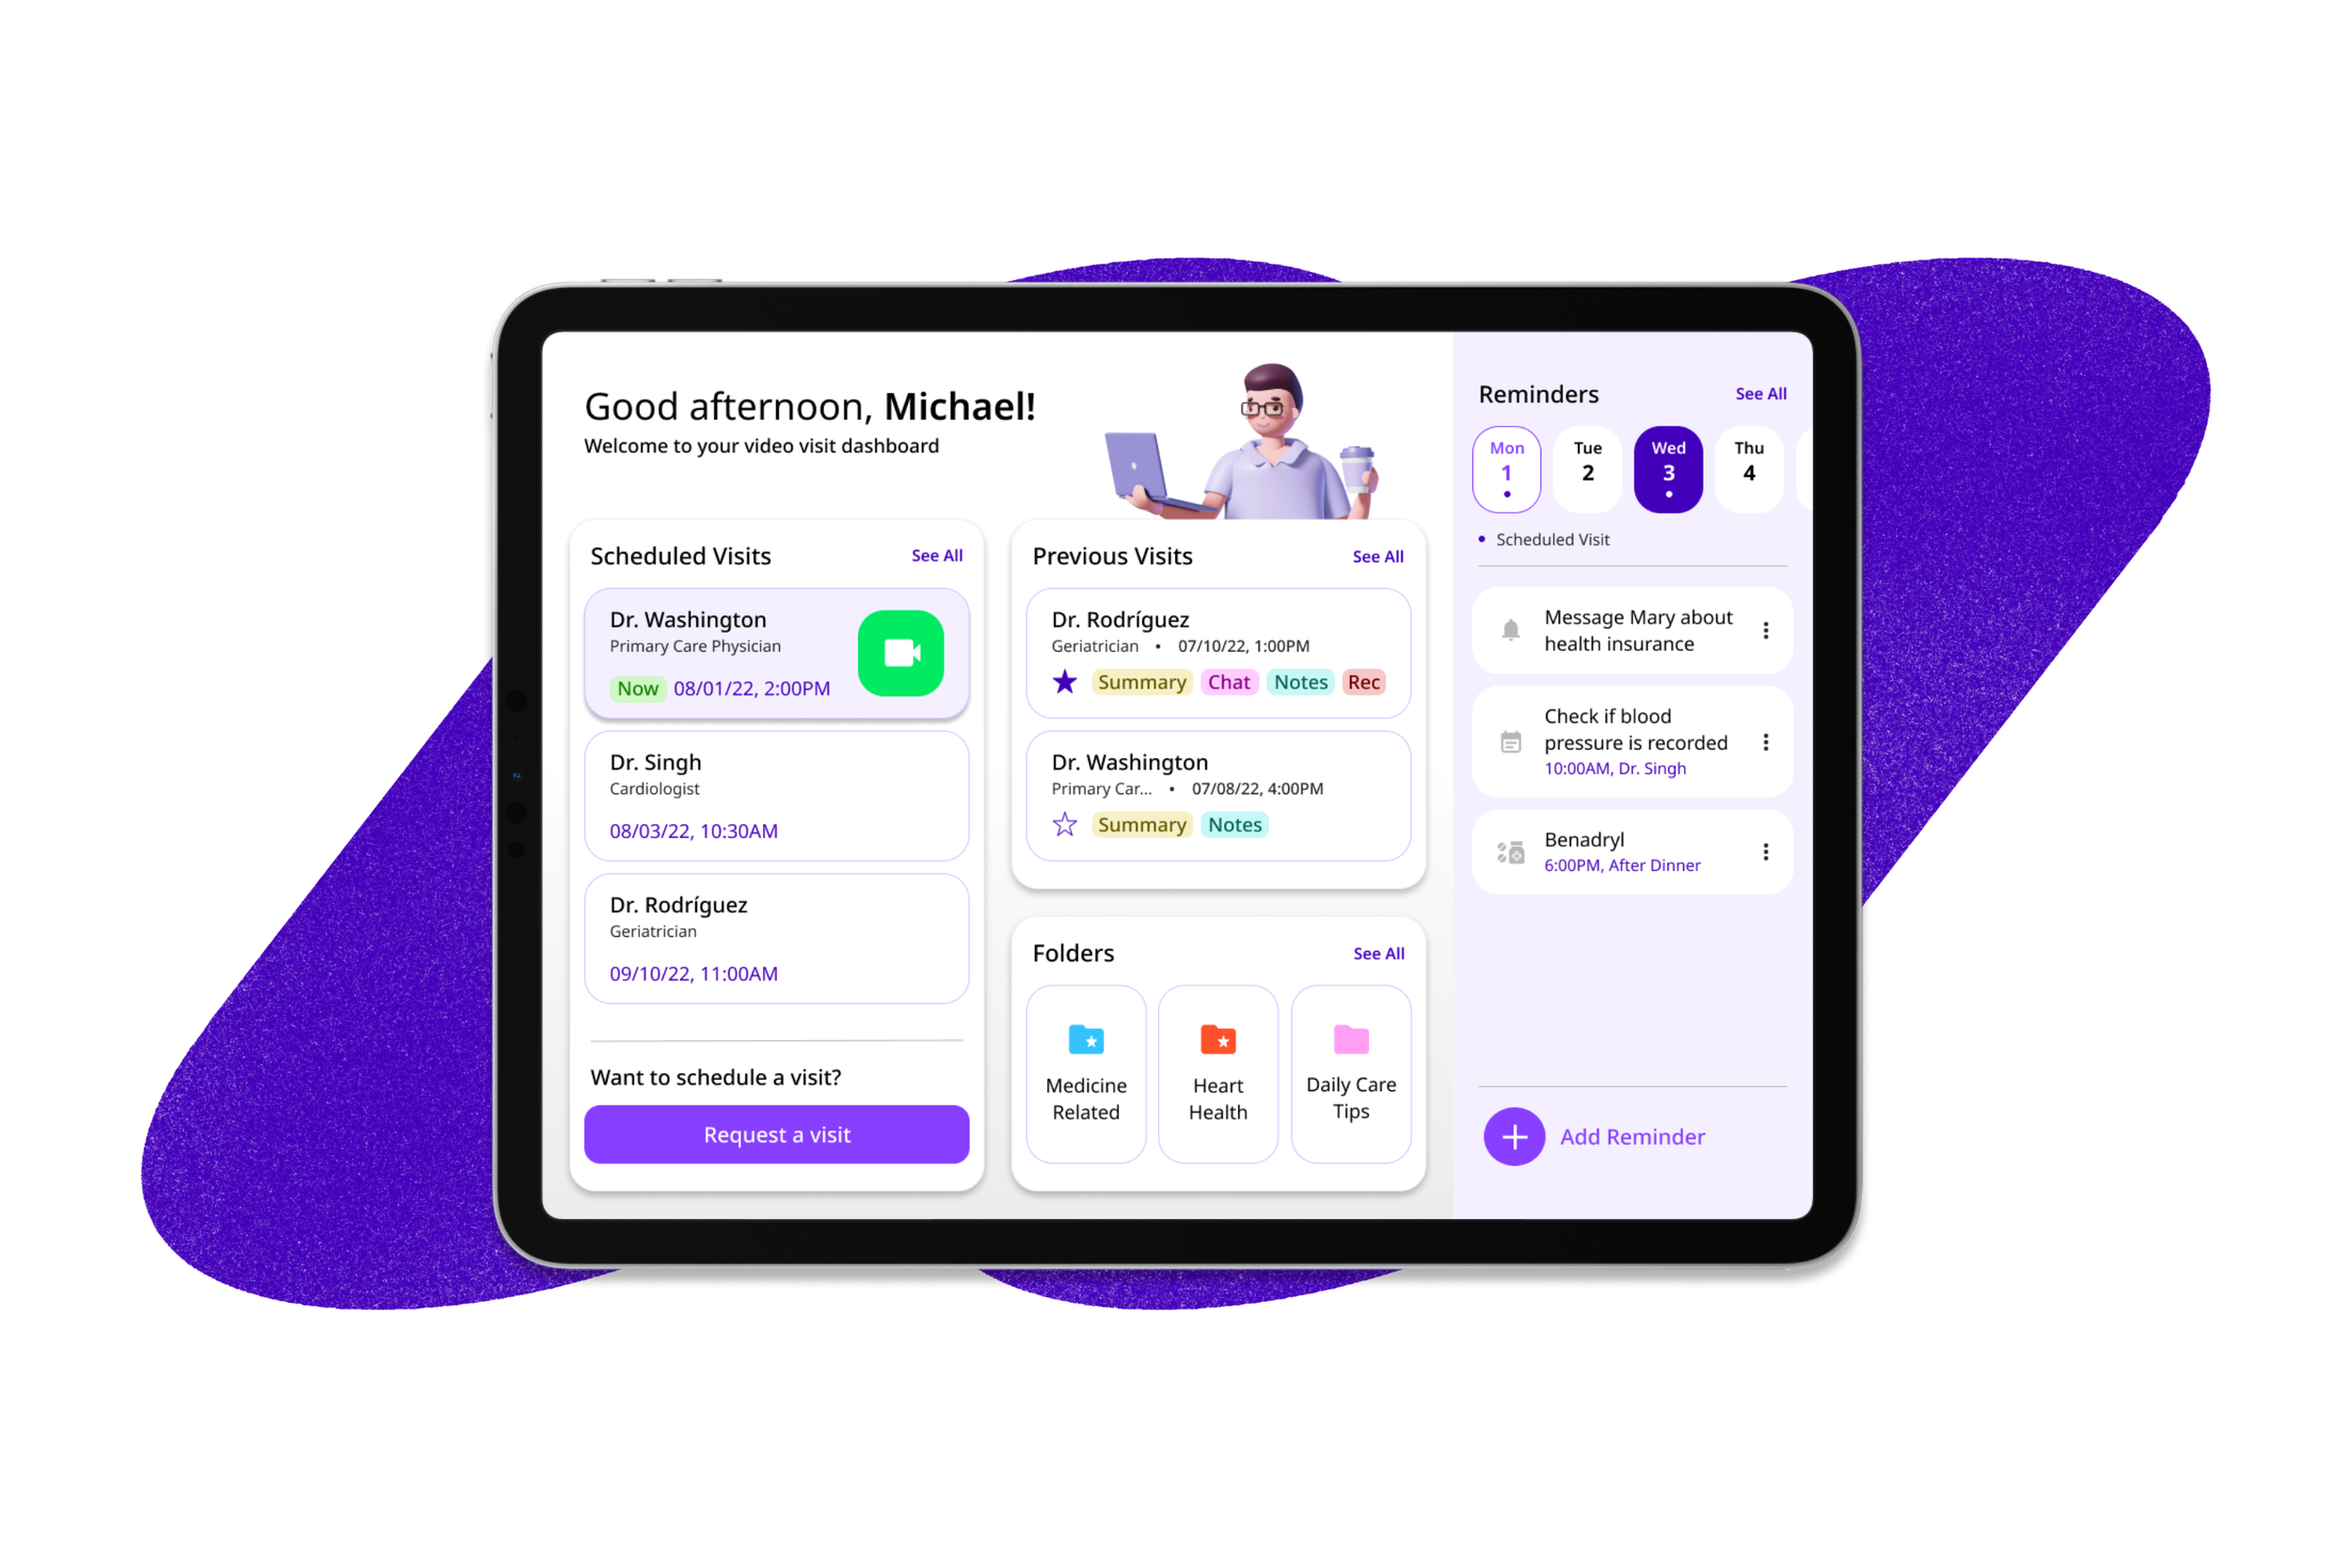

Product and Visual Designer with a drive to turn narratives and complex problems into beautiful, user-friendly solutions.

I’m a designer who enjoys experimenting around and creating narratives through visuals.